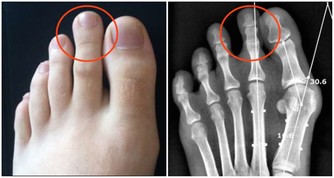

類型2/進食方式: 進食速度過快,或是在用餐過程中不斷說話,都可能導致吞嚥時,吸入大量的氣體,一旦累積到一定的量,便會以打嗝或放屁等方式排出。 類型3/腸道狀態: 正常人的腸道中或存有大量的細菌,來幫助人體維持消化功能的運作,可是,當身體狀態不佳、飲食長期不均衡時,腸胃道中的好壞菌比例便會失去平衡,使容易產氣的壞菌大幅增加,自然就會產生頻繁排氣的症狀。 類型4/腫瘤阻塞: 此外,大腸癌患者因腫瘤組織堵塞部分腸道,影響腸道蠕動造成積氣,也是導致「連環屁」、放屁次數大幅提升的原因之一。不過,值得注意的是,腫瘤要長到一定的大小,需要很長的一段時間;因此,此類症狀多出現於大腸癌後期的患者身上。 常放臭屁,是大腸癌前兆?醫:傳言不可信! 有鑒於此,「常放臭屁,恐是大腸癌前兆」的謠傳,其實並不完全正確,陳樞鴻醫師指出,除了屁臭不臭不是重點外,更不是大腸癌的「前兆」,反倒是大腸癌末期的病友較可能發生。

且頻頻放屁的症狀,也並非是所有腸癌患者都會出現。人體的腸道結構,主要除了居中的橫結腸外,又可區分為右大腸(升結腸、盲腸)、左大腸(降結腸、乙狀結腸、直腸)兩區塊。其中,右大腸(升結腸、盲腸)因彈性較佳,因此一旦癌細胞從此而生,往往患者發現時,腫瘤已變得相當大,且症狀上多以貧血較為常見。 至於放屁症狀,則較容易發生於,腫瘤組織位於後段左大腸(降結腸、乙狀結腸、直腸)部位的癌友身上。特別是大腸直腸癌者,由於直腸較接近肛門、管腔小,即便腫瘤不大也容易發生阻塞,因此引起放屁頻頻、腹痛、腹脹、便祕等症狀的機率自然較高,也較易有血便問題,發現率也較前者來的高。 【醫師小叮嚀】: 陳樞鴻醫師提醒,想要防範大腸癌上身,民眾應養成良好、規律的飲食及運動習慣,盡可能維持正常作息;至於50歲以上的人,更要定期接受國民健康署建議的「糞便檢測」,早期發現、早期治療,自然健康有保障!